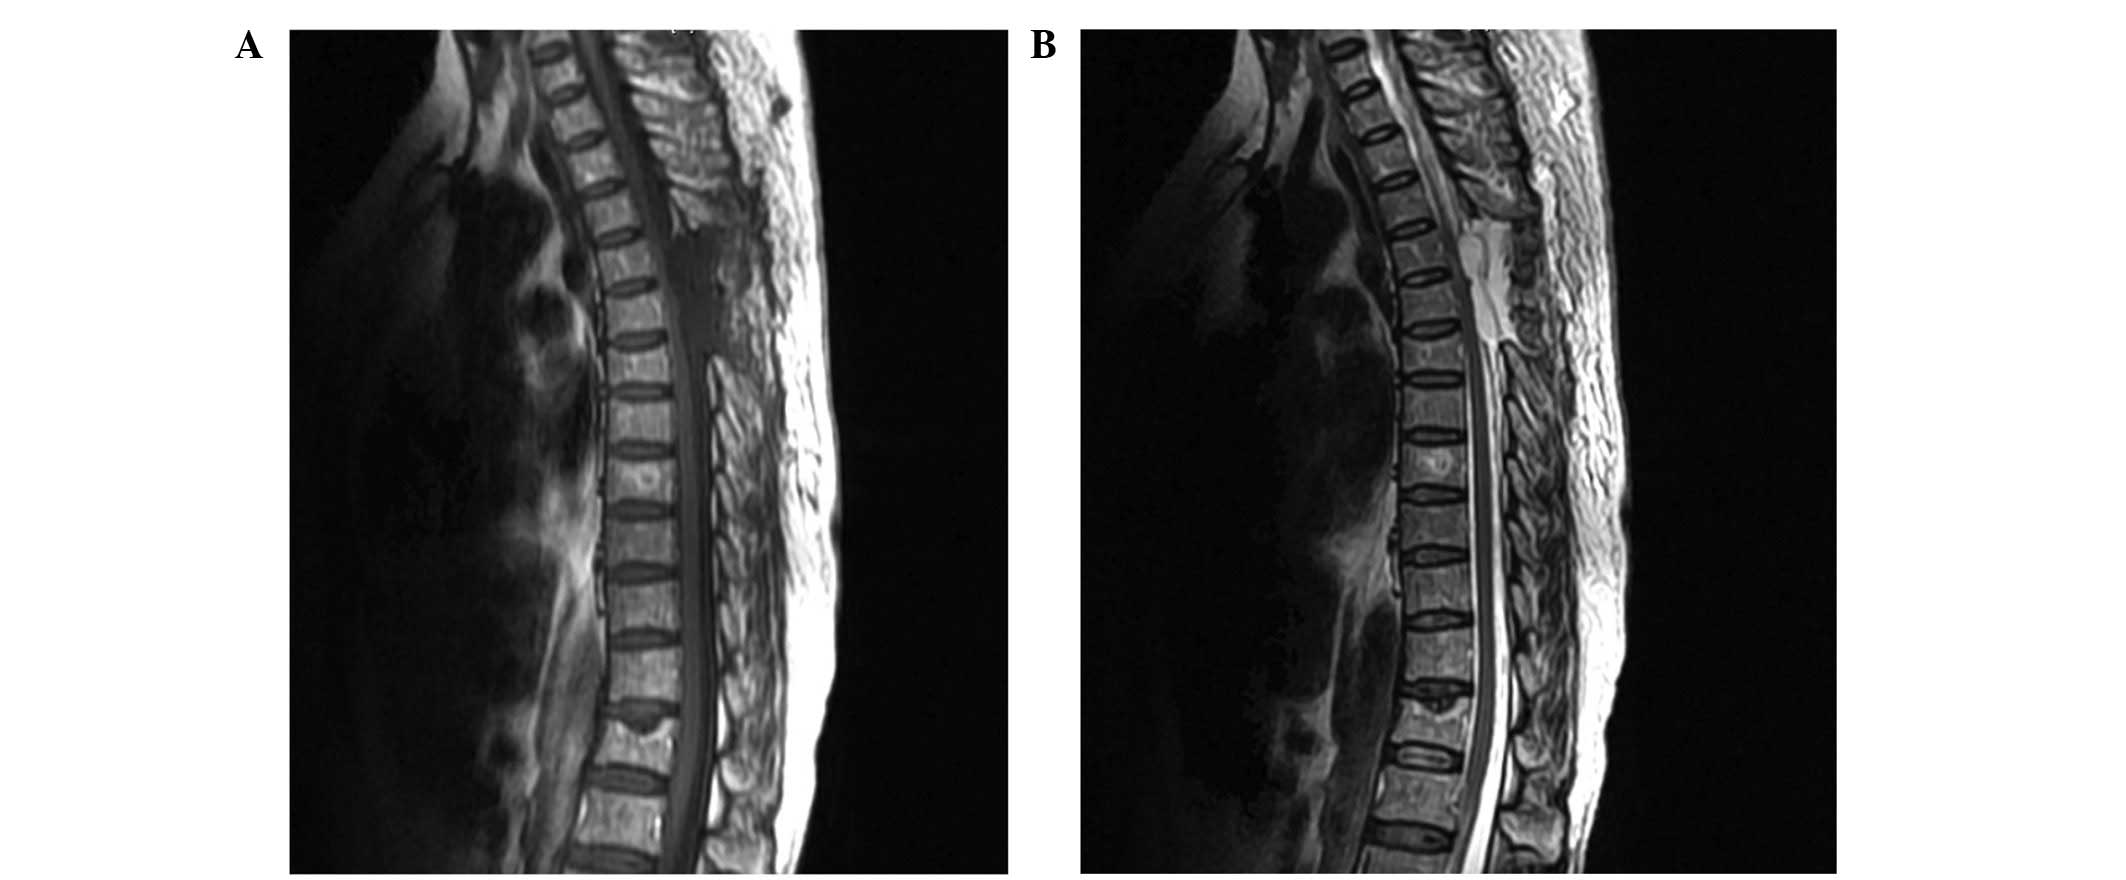

A postoperative clinical examination of the patient revealed no loss of motor capacity or decrease in motor strength. Repeated MRI scans of the thoracic spine, conducted one week after surgery, demonstrated that the mass had been totally resected (Fig. 2). The patient was transferred to the oncology department for chemotherapy, and was followed up by the medical oncology and neurosurgery departments.